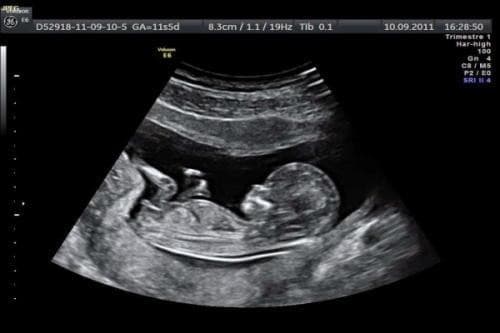

Đo độ mờ da gáy được tiến hành khi thai từ 11-14 tuần tuổi. Nếu thực hiện quá sớm, kết quả đo sẽ mờ, không cho kết quả chính xác. Còn nếu để quá thời gian này, độ mờ da gáy lại trở về bình thường vì chất lỏng gáy dư thừa sẽ được hệ thống bạch huyết của bé hấp thụ. Mức độ mờ da gáy sẽ giúp mẹ xác định được nguy cơ mắc bệnh down ở thai nhi. Những thai nhi có khả năng mắc hội chứng Down, lượng chất lỏng dưới da ở mặt sau cổ nhiều hơn trẻ bình thường.

Thai 12 tuần độ mờ da gáy bao nhiêu? Kết quả đo độ mờ da gáy khi thai 11 tuần thường là 2mm, 13 tuần thường là 2,8 mm. Đây là hai chỉ số cho biết thai nhi bình thường. Trường hợp độ mờ da gáy lớn hơn 3mm, bé có nguy cơ mắc hội chứng down. Thông thường, qua độ mờ da gáy bác sĩ có thể phán đoán 75% nguy cơ trẻ bị down.